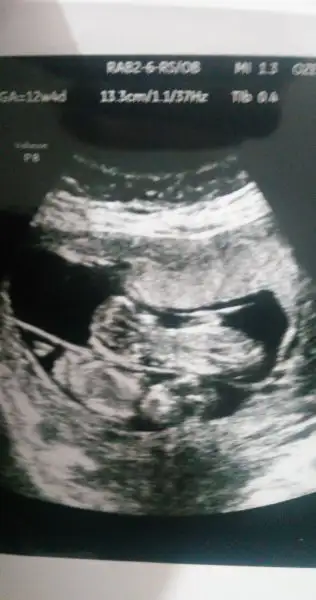

Bugün kontrolüm vardı 4 cm olmuş miniğim. Bıcır bıcır oynuyordu :) 2 hafta sonra 2li test yapılacakmış. Ben kilo vermişim bebişin beslenmesi iyi ama böyle devam etsem en kötü yeter sanırım.